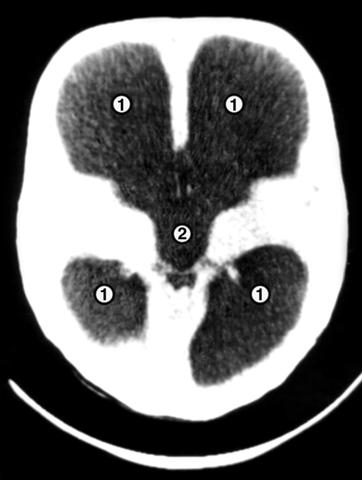

Рис. 4. Компьютерные томограммы головы грудного ребенка с гидроцефалией: на срезах, выполненных на разных уровнях, видно резкое расширение боковых (1) и третьего (2) желудочков.